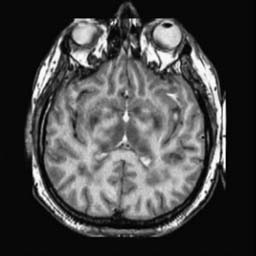

To demonstrate the effectiveness and efficiency of the proposed image fusion method , we conduct a set of comparative experiments on three image datasets. The first is composed by 8 pairs of multi-modal medical images and the second one contains 15 pairs of multi-focus gray or color natural images. These two datasets are often used in many related papers and some examples are shown in Figure 3(a) and Figure 3(b). The third one is a new multi-focus cervical cell image dataset collected by ourselves, which consists of 15 groups of color images and each group contains a series of multi-focus cervix cell images with size of or , etc. Some source examples are shown in Figure 3(c). Our source code implemented in C++ along with the new multi-focus cervical cell image dataset is available online.

We first evaluate the performance of the proposed method under varying total number of octaves and number of layers sampled per octave. The fused images of a pair of multi-modal medical images with different and are shown in Figure 4. In this example, on the one hand, when only 1 or 2 octaves are involved in constructing the DoG pyramid, the fused images fail to keep the integrity information of large size objects (e.g. eyeballs), while by increasing the value of , the integrity information of eyeballs is preserved. On the other hand, although not as significant as the increase of octave numbers , the fused image can contain more details by the increase of layer numbers . The corresponding objective quality metrics are shown in Figure 5. As shown in Figure 5(a), most of the metric values are improved as the number of octaves increases with the fixed layer numbers 3 in the global tendency and each of them tends to be stable when the number of octaves is 5. To get a relatively good quality from Figure 5(b), we can notice that some of the metric values can get a good performance when the number of layers is 3, such as the MI, SSIM, QI and VIF, though there are only a little change of all the metric values by increasing the number of layers with the fixed octave numbers 5. Because it will result in more computation burden with the increase of the value and , and for different kinds of source images, there are different performance with the diverse parameter settings. To get a trade-off between them in our experiments, we set for the multi-modal dataset, for the natural datasets and for the multi-focus cell dataset, respectively.

Figure 6 shows the fused images obtained by different methods with the multi-modal source images shown in Figure 3(a). As shown in these figures, the proposed method can produce images which preserve the complementary information of different source images well. Moreover, due to the scale-invariant structure saliency selection, our method can keep the integrity information of large size objects and the visual details simultaneously. Although the fused image generated by other methods can also capture the details to some extent, all of them fail to keep the integrity information of large size objects such as the eyeballs. Furthermore, from Figure 6(k)-6(t), the DTCWT, GFF, IM and NSCT methods may decrease the brightness and contrast while the proposed method can preserve these features and details without producing visible artifacts and brightness distortions.